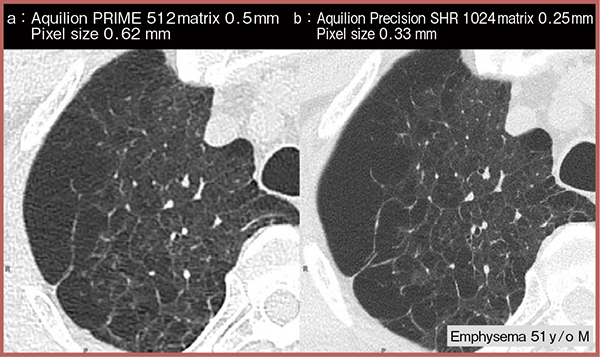

続いて登場した高精細CT「Aquilion Precision」は,従来CTの1/4の検出器画素サイズを実現,空間分解能が0.15mmに向上した。マトリクスサイズも従来CTの512×512マトリクスに対し,1024×1024マトリクスの微細な画像の取得が可能になった(図2)。細気管支炎症例での小葉中心性斑状影の内部構造や,造影CT画像上の血管側枝や微細な気管支なども明瞭に確認できる(図3)。また,死亡時画像診断(Ai-CT)で線量を制限せず1秒/回転で撮影したところ,内径0.4mmの細気管支まで描出可能であった。

図2 従来CTと高精細CTの比較